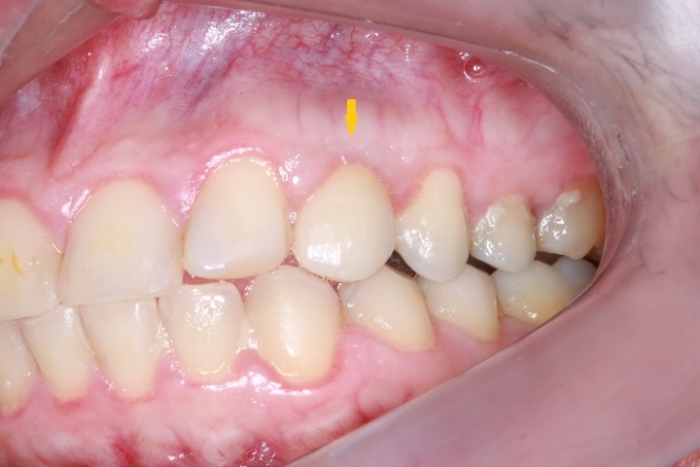

Imagem inicial com presença de canino decíduo